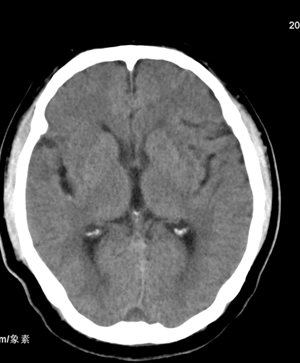

肢体活动肌力均正常。临床印象:脑血管病变。ct意见:脑软化灶,腔梗,请看看枕部病变是脑膜瘤,血管畸形还是其它

不象是软化灶.考虑水肿,病灶内有钙化,建议增强.

颅骨吸收破坏,病灶密度不均,周围见低密度水肿带,多考虑恶性脑膜瘤。

枕骨骨质吸收破坏,局部病灶密度不均,周围见低密度水肿带,考虑脑膜瘤,建议增强扫描。